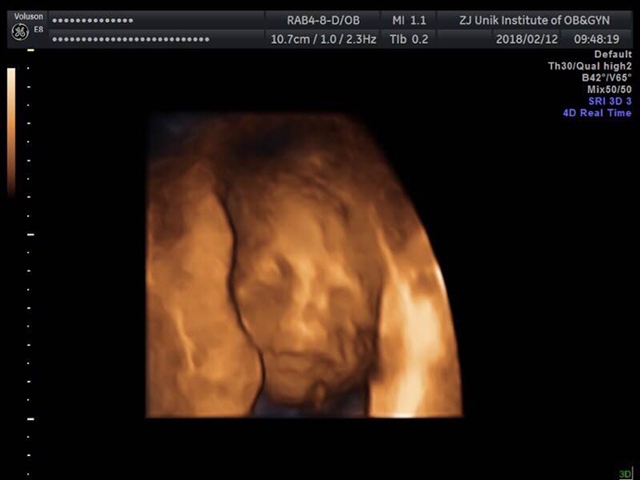

孕13周+1天

女孩

徐雨雨[帖主]:男孩